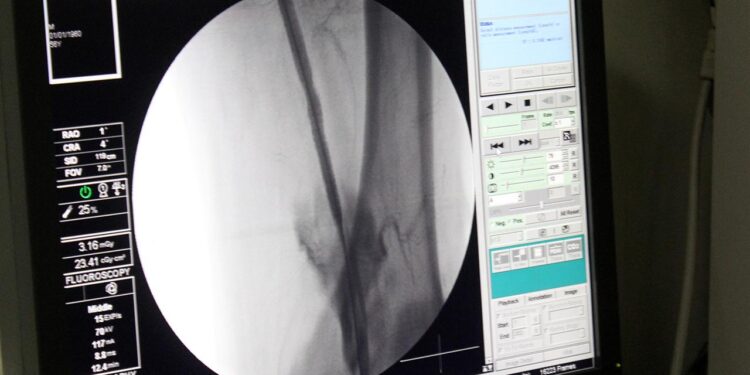

Nihai tasarımlarının, bir prostetik venöz kapakçığın neden olduğu en düşük kayma hızı olduğunu ve bu sonuçlar, etkin bir klinik tedavi şekli potansiyeline sahip olduğunu dile getiren uzmanlar, bu işlemin bir kateter vasıtasıyla anjio altında damara girişim yapılarak kolaylıkla implate edilebilecek bir şekilde tasarladıklarını ifade ediyor.

İşlem minimal invaziv yöntemlerle uygulandığından uzun sürmemekle beraber hasta yatış süreleri mevcut tedavi yöntemlerine göre oldukça düşük olduğu belirtiliyor.